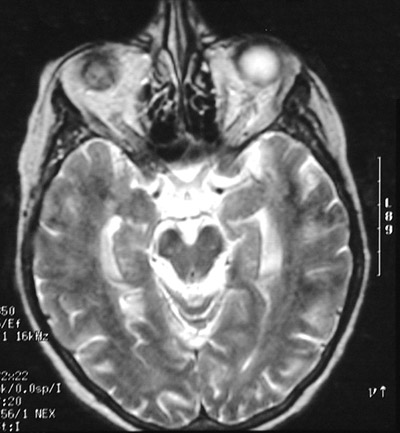

| The T2 weighted MRI scans in axial view above and below show areas of brightness at the base of the brain, particularly around the brainstem, as a result of a carcinomatous meningitis. This is an uncommon pattern of metastases in which the tumor diffusely infiltrates the meninges, either with or without a mass effect. |